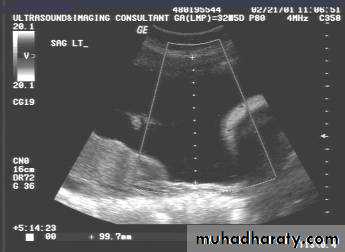

UUUUUUs of pelvic organs :

Ovarian cysts :

Ovarian cysts are commonly encountered in gynecological imaging, and vary widely in etiology, from physiologic, to complex benign, to neoplastic.Small cystic ovarian structures should be considered normal ovarian follicles unless the patient is pre-pubertal, post-menopausal, pregnant, or the mean diameter is >3.0 cm

Radiographic features

Ultrasound is usually the first imaging modality for assessment of ovarian lesions. Simple ovarian follicular cysts are:

anechoic

intraovarian or exophytic;

have an imperceptible wall